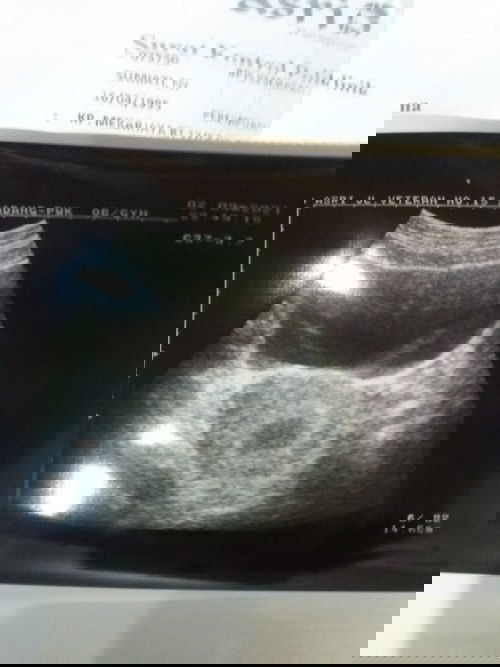

Dikira hamil 4 bulan ternyata baru 6 minggu itupun baru kantung kehamilan

Telat sampai 4 bulan sempat flek coklat 5 hari

ini lah Bun pentingnya USG di awal kehamilan,supaya ga terjadi seperti ini😊kalau sudah telat haid dan tespeck positif langsung USG biar perhitungan nya sama,kalau udh begini kan jdi bingung apa lg sebelumnya sempet flek,dibilang janin ngga berkembang pun kita gtw karena dri awal blm pernah usg,semoga aja EMG bner kandungannya msih 6 week ya Bun❤️dan semoga di usg selanjutnya sudah ada janinnya dan berkembang dengan sehat,doa yg terbaik utk bunda❤️🤗

kalo saya kehamilan 7mgg masih kantung aja yang membesar, disuruh nunggu bberapa minggu lagi😌 semoga kita semua diberikan kelancaran ya bunda ..